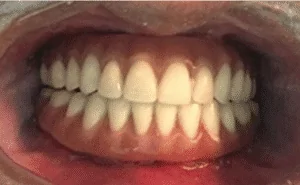

Paciente de 48 anos, do sexo feminino, apresentando boa saúde geral, procurou atendimento odontológico para reabilitação maxilar. A mesma relatou